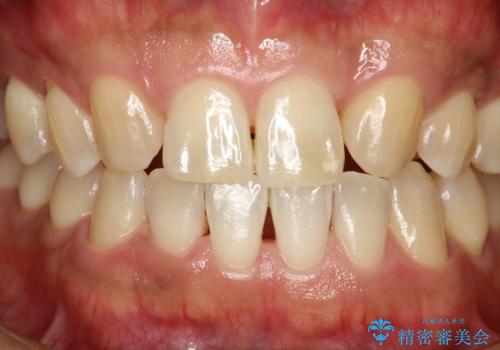

- 全体的な着色(ステイン)、黄ばみが気になるとのことで、来院されました。着色(ステイン)などの付着量が多かったためPMTCの60分コースを行いました。

PMTCを行うと、着色(ステイン)や歯石などを除去することができます。

PMTCは、歯科医院にて専門的な機械・材料を使用して行う専用クリーニングです。着色(ステイン)や歯石を取り除くことで、ご自身の本来の歯の色となります。また、施術後にはスッキリとした爽快感あ得られたり、歯の舌ざわりがツルツルになり気持ちがいいです。